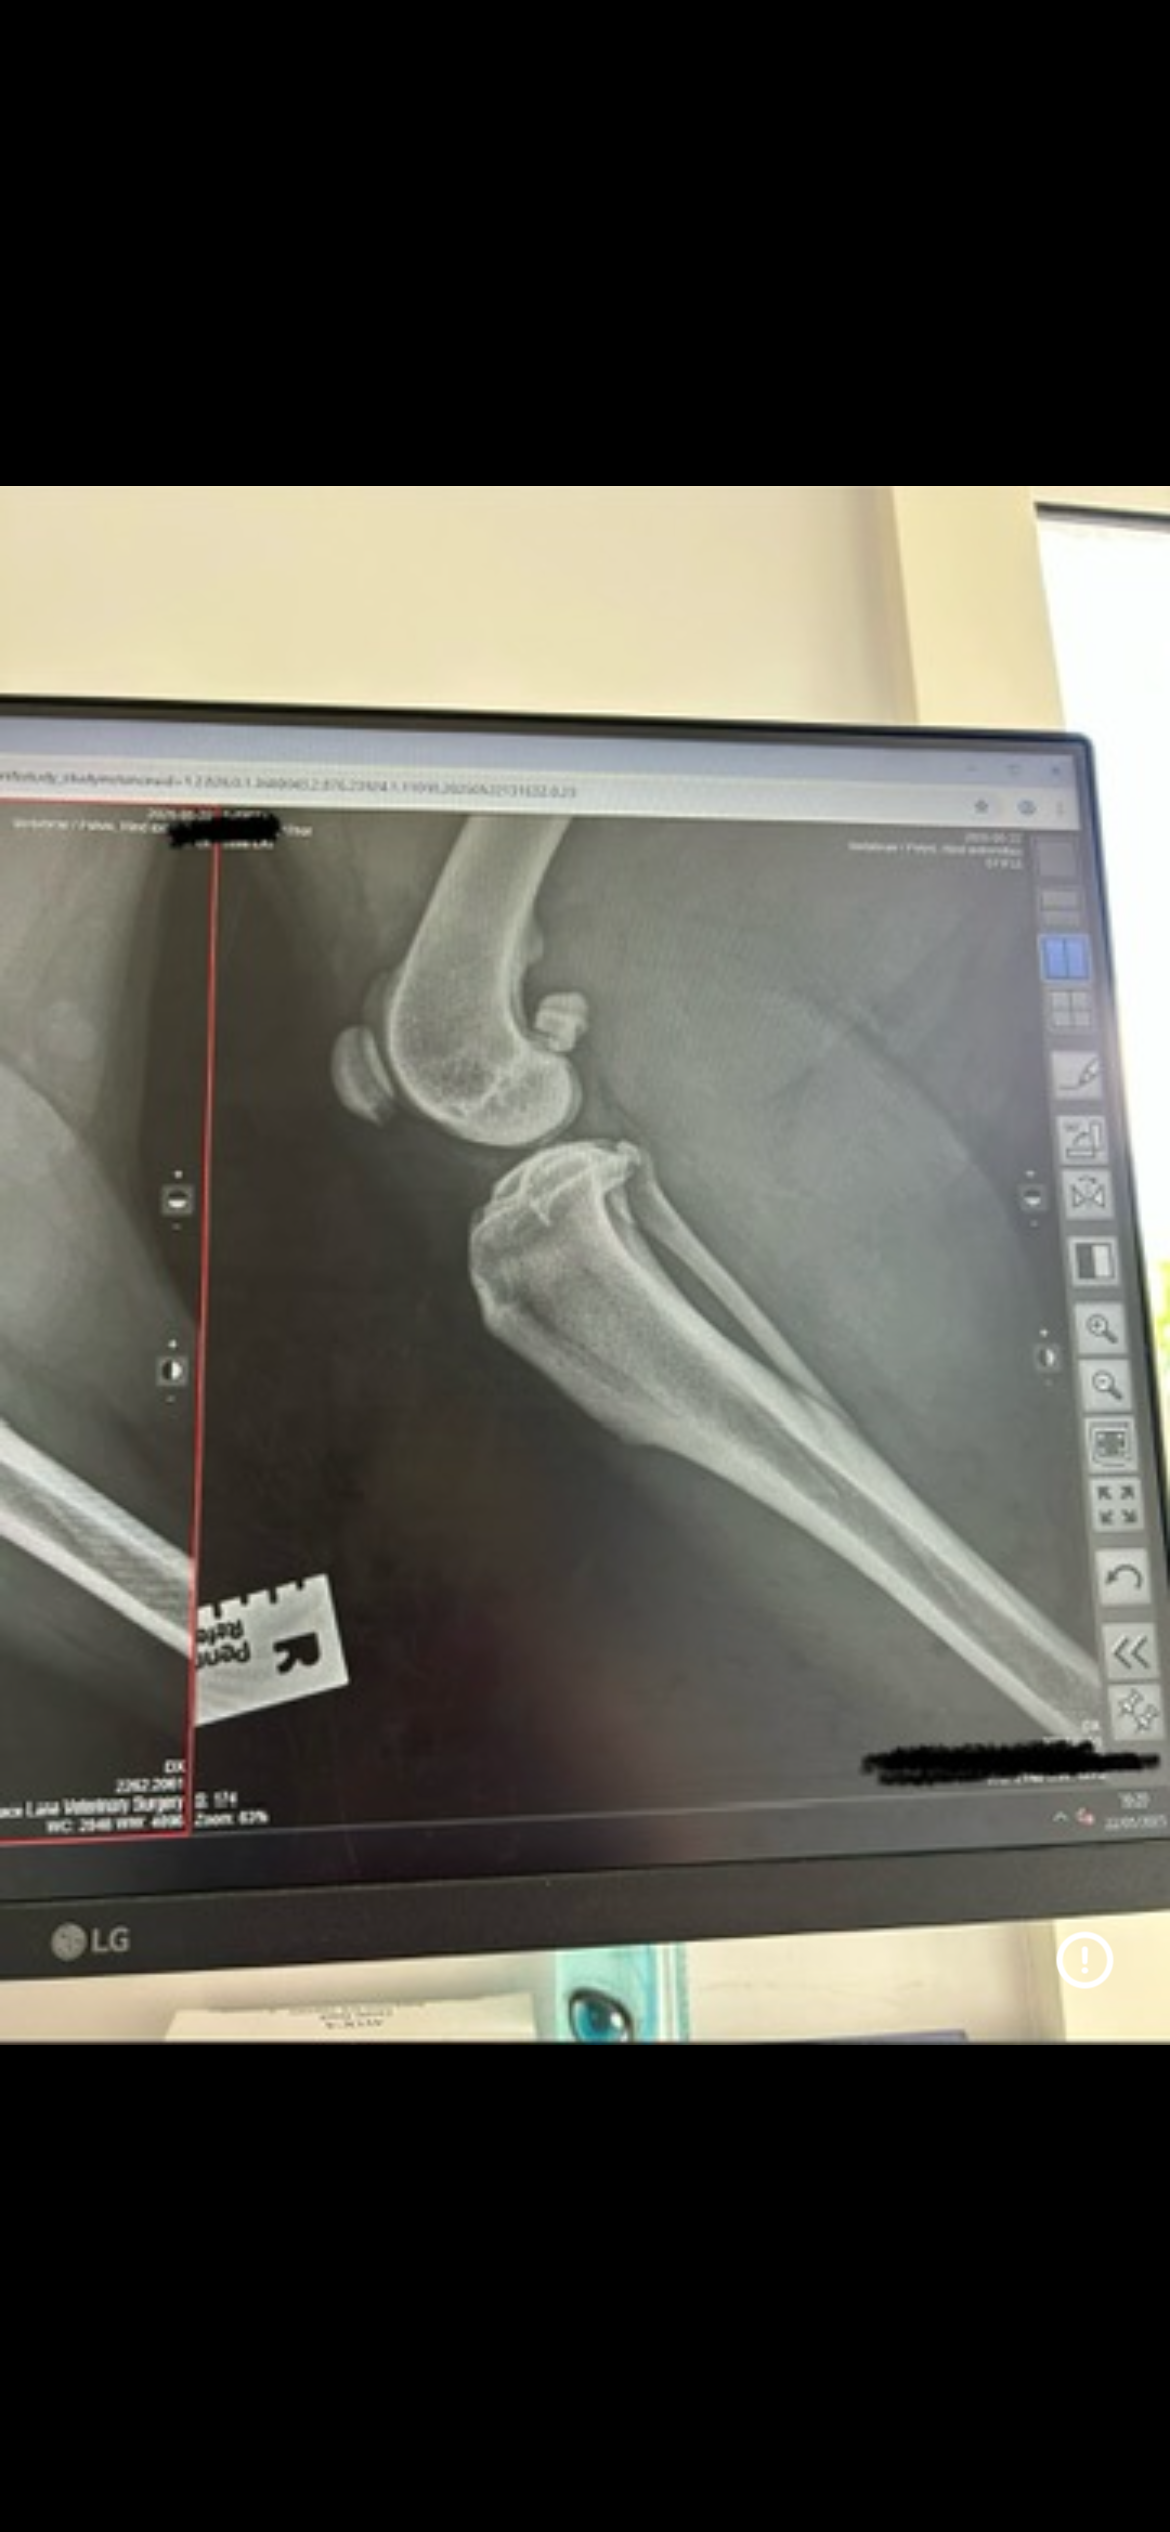

I have hip dysplasia and osteoarthritis, and my x-rays showed that the ligament in my left back leg is torn. The vets said that without TPLO surgery, I will never be able to walk properly again.